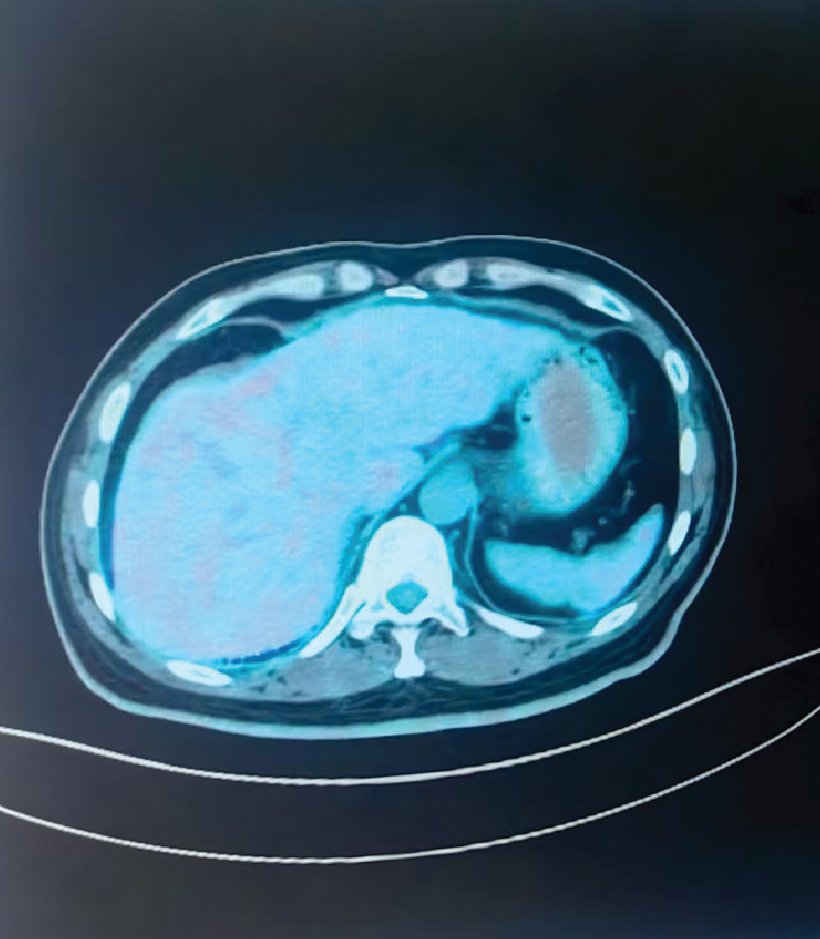

Before Treatment (Liver)

2-Month Follow-Up